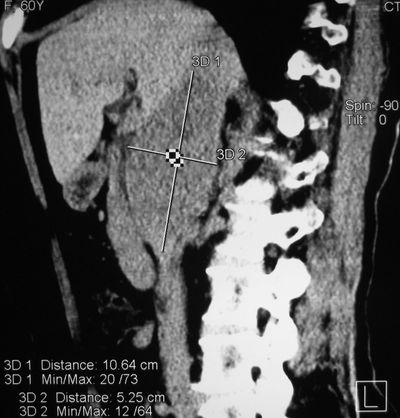

Компьютерная томограмма